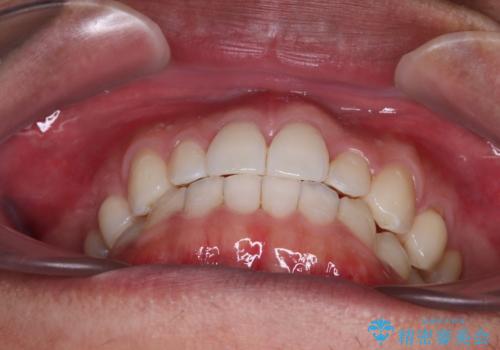

前歯のデコボコとクロスバイト インビザライン矯正治療

- 前歯のデコボコとクロスバイトを治したいとのことで来院された患者様です。

上下顎ともに歯列全体の側方拡大を行い、下顎前歯はIPR(歯と歯の間を削る)によってデコボコとクロスバイトが解消するように設計し、インビザラインにより治療を行うこととしました。

2年弱で終了する予定でしたが、途中来院されなかった時期があり、その後舌側転位している前歯を動かせるところまで動かしたいとのことで4年ほど治療を継続されました。